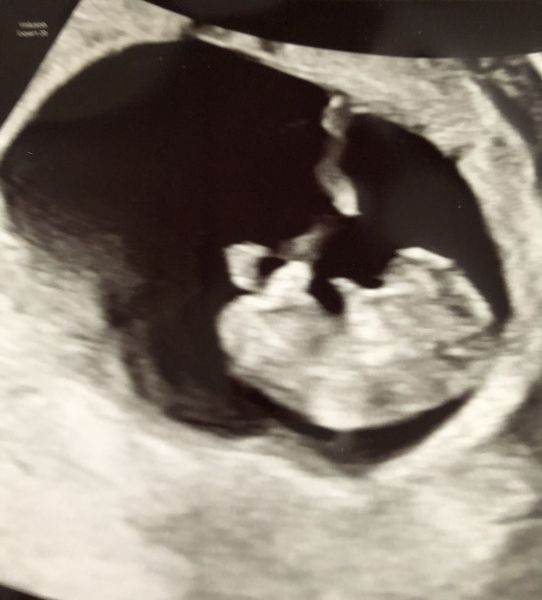

CosmicLove · 29/07/2024 09:56

Morning ladies, pleased to report all well with my scan this morning! Measuring 9+3 which I am today and heartbeat a strong 170. Little limb buds waving around which was lovely to see. We're over the moon ❤️

Beks96 · 29/07/2024 10:11

@CosmicLove Absolutely beautiful, so happy for you 🥹💖